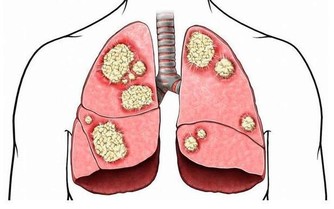

人在強烈悲哀時,會出現呼吸頻率改變、乾咳、氣短、音啞等症狀。

現代醫學則發現,悲傷時,人體交感神經系統分泌出大量壓力激素,增加心髒病發作風險。